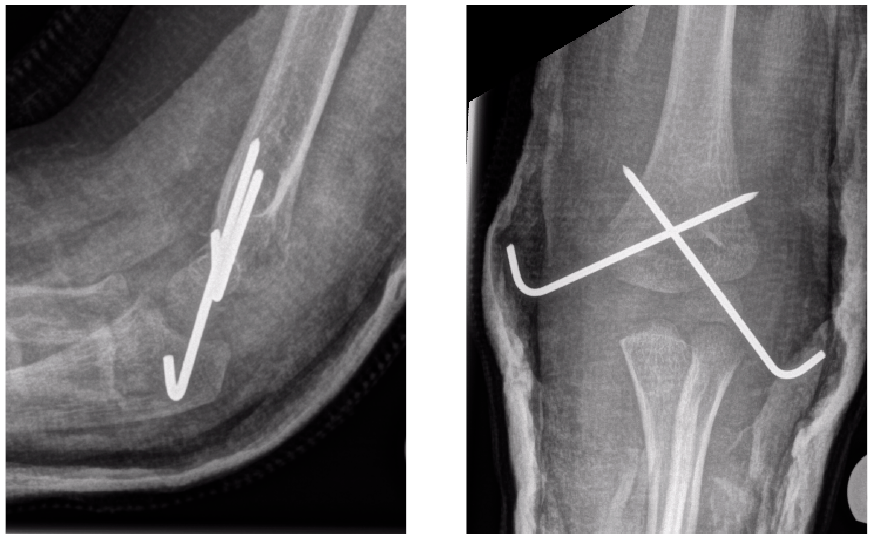

Your child has had a broken bone which had to be realigned to a good position and be fixed with wires to maintain the position.

The wires usually stick out of the skin so that they can be easily removed, once the bone has healed. They are covered with padding and a plaster cast and your child will not be able to see or feel them.

An x-ray may be needed to confirm the fracture has healed enough for the wires to be removed.

The plaster cast will then be removed in the Plaster room. This does not hurt but the noise and vibration of the plaster saw can be alarming for young children. Once the cast and dressing have been removed, the wires can be seen sticking out of the skin. Please reassure your child that this is normal.